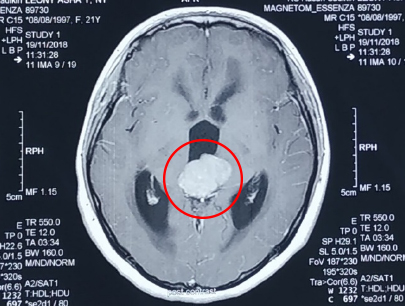

(Perempuan 22Tahun)

Diagnosis: Tumor Pineal

Sebelum Gamma Knife

• Nyeri Kepala

• Pandangan Ganda

• Gangguan Gerak Bola Mata

3 bulan Setelah Gamma Knife

• Pandangan ganda tidak ada

• Gangguan gerak bola mata perbaikan

Catatan: pasien menjalani operasi VP Shunt

Volume Tumor: 25,7 cc

Volume Tumor: 3 cc